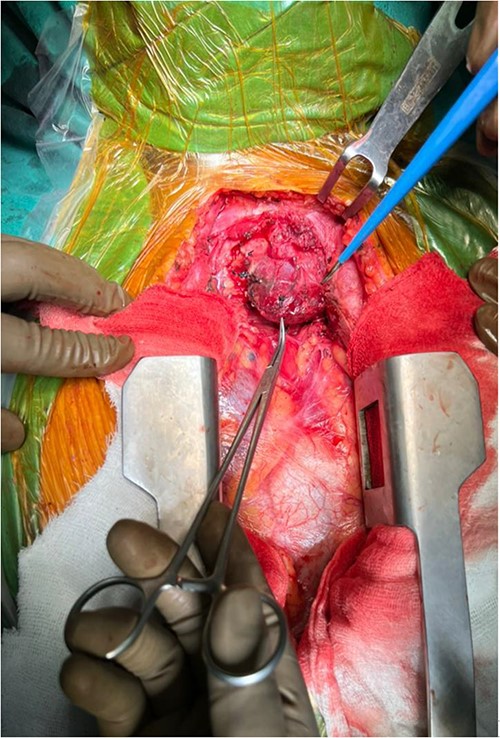

The right mass (Fig. 5) was even bigger and needed an extension of incision into the neck (Fig. 6). About 7 cm × 7 cm noted to be displacing Superior venacava anteriorly that was dissected from it, separated from the first rib and subclavian artery meticulously taking care not to damage any major structure. Both masses were excised. These masses were not connected in any way with each other as well as with the orthotopic thyroid in the neck. Post-op was uneventful. Thyroid functions were normal. Thyroid scan (Fig. 8) showed no evidence of a thyroid tissue in the mediastinum and no other ectopic thyroid was present other than the orthotopic thyroid tissue in neck. The patient was discharged on POD 10 without any symptoms. The histopathological tissue diagnosis showed a colloid goiter (Fig. 7). All data kept in our database.